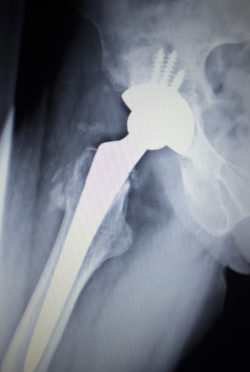

y tones. Scanned in orthopedics traumatology surgery hospital clinic.Depuy Orthopaedics is facing a new metal hip implant lawsuit from a South Carolina couple, alleging the company’s all metal hip implants caused the wife serious and permanent harm.

Diana had opted on the DePuy ASR hip implant as her choice of hip replacement, after consulting her doctor. However, soon after having the DePuy metal hip implant inserted on June 12, 2008, Diana began experiencing implant complications.

Laboratory testing also indicated Diana was suffering from blood metal poisoning, or metallosis, based on elevated cobalt levels. Diana eventually had to undergo revision surgery on March 30, 2015, removing the DePuy metal hip implant.

According to the operative report, there was fluid in the hip joint, fibrous material in the hip capsule, and severe corrosion.